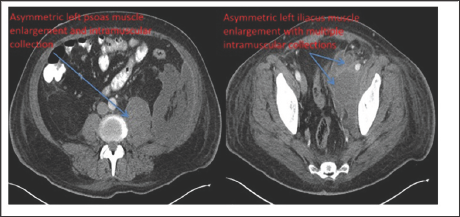

Two days later he complained of new blurry vision in the right eye and was found to have a hypopyon and vitreous inflammation on exam with a VA of 20/200. This eye was diagnosed with endophthalmitis and treated with vitreous tap and intravitrealvancomycin and amikacin. Both vitreous samples grew MSSA. We discussed with the primary team that further efforts should be done to find the source of the bilateral endogenous endophthalmitis. A transesophageal echocardiogram was unremarkable. The patient was still having persistent abdominal pain since presentation, which was initially attributed to the STEMI, so a CT-scan of the abdomen and pelvis was performed revealing a large left-sided psoas abscess which was drained with cultures being positive for MSSA (Figure 2).

Figure 2: Axial cut of computed-tomography imaging of the abdomen and pelvis revealing a large left-sided psoas abscess demonstrated by the blue arrows.